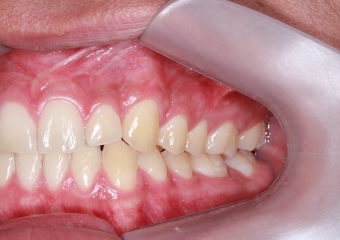

Intra oral - Caninos em posição - Clínica Cliniface

Intra oral - Caninos em posição